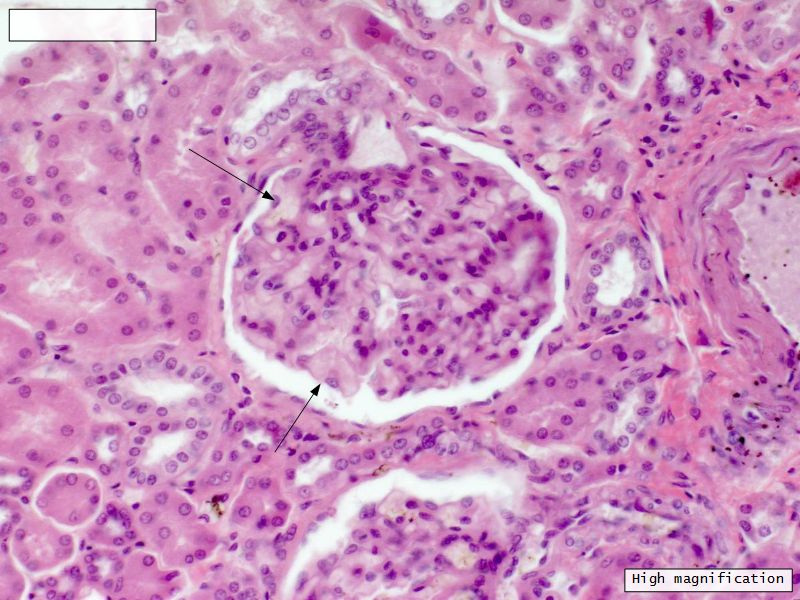

Renal corpuscle

• Tuft of capillaries

• grow into

• Blind end of nephron

• Several layers of epithelium

• Two sides

• Vascular pole

• Tubular pole

Epithelium layers

• Capillary endothelium

• Visceral layer of epithelium

• Podocytes

• Resting on glomerular basement membrane

• Capsular space

• Parietal layer of epithelium

• Simple squamous epithelium